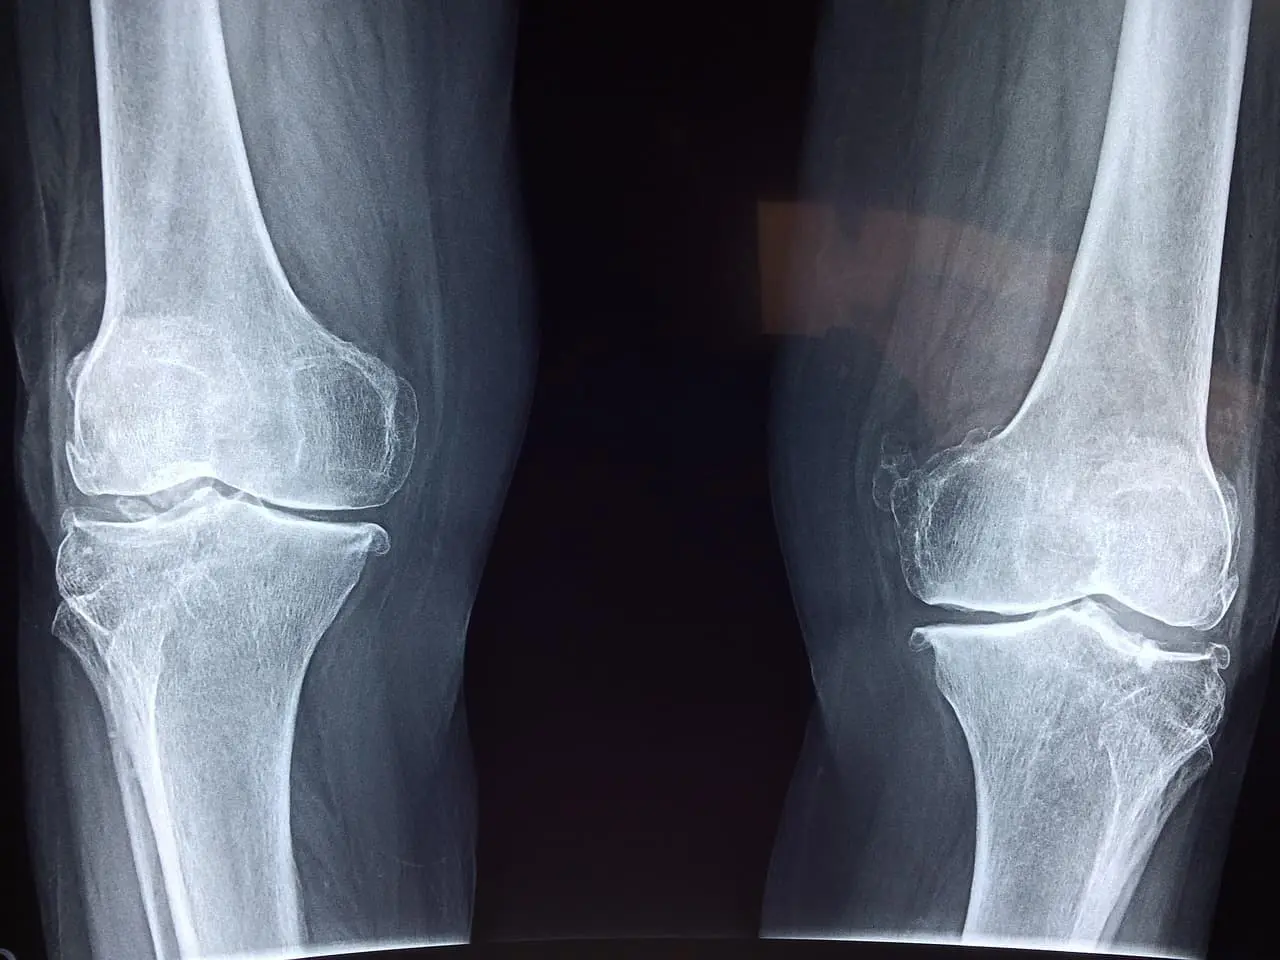

골다공증 치료를 위해 병원을 찾은 많은 환자들이 처음 겪는 혼란은 “왜 내가 원하는 약을 바로 사용할 수 없지?”라는 부분입니다.

이처럼 현재 국내 건강보험 시스템에서는 치료 효과와 접근성 사이의 ‘절충’을 환자에게 강요하고 있습니다.

건강보험 적용의 문제점 – 현실과 제도의 괴리

1. ‘65세 이상 + 골절 2건 이상’만 보험 적용

- 환자가 실제로는 60대 초반, 첫 골절이 발생한 시점에 적극적 치료가 필요하지만

- 현행 제도는 이미 두 번 이상 골절이 발생한 이후에야 치료 전환을 허용합니다.